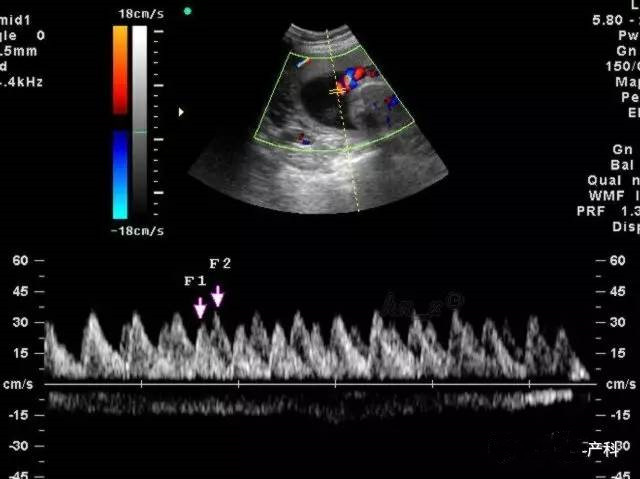

正常值跟怀孕的周数有关,主要有三项,以S/D值为主要指标,多以妊娠晚期S/D值小于或等于3.0作为正常值.脐血流和孕周时间有着密切的关系,一般随着孕周的增加,脐血流呈降落趋势,脐血流正常值在24周时其平均值为3.5,上限为4.25,超过此值为异常。可以使用脐动脉血流检测仪,在胎儿肢体侧探测脐动脉血流,内置软件根据所测S/D,PI、RI、FUR血流指标将自动测出血流阻抗分级。

S/D:脐动脉血流速度峰谷比

正常妊娠时胎儿的S/D、RI值随着妊娠时间推移呈降低趋势,尤其S/D值的变化是掌握胎儿发育是否正常的重要指标。